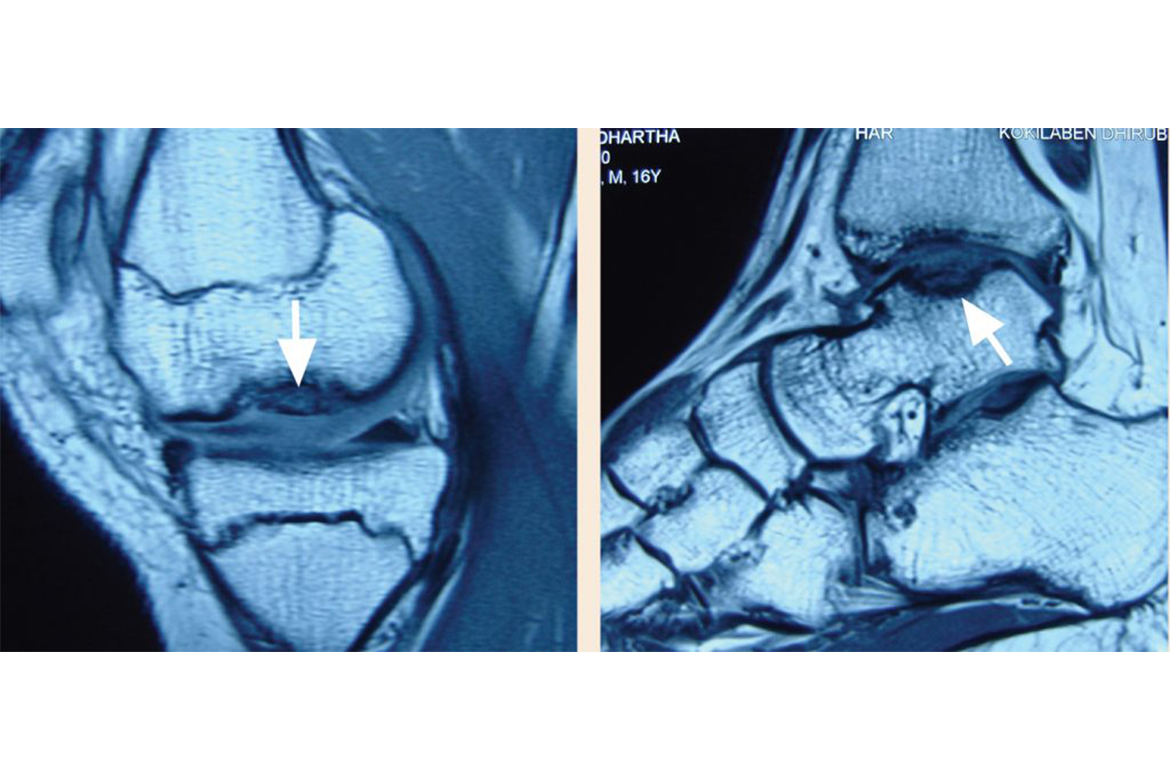

A 16 year-old athlete was referred to the hospital with pain, swelling and episodic locking of the left knee and left ankle which he had twisted during a basketball match…